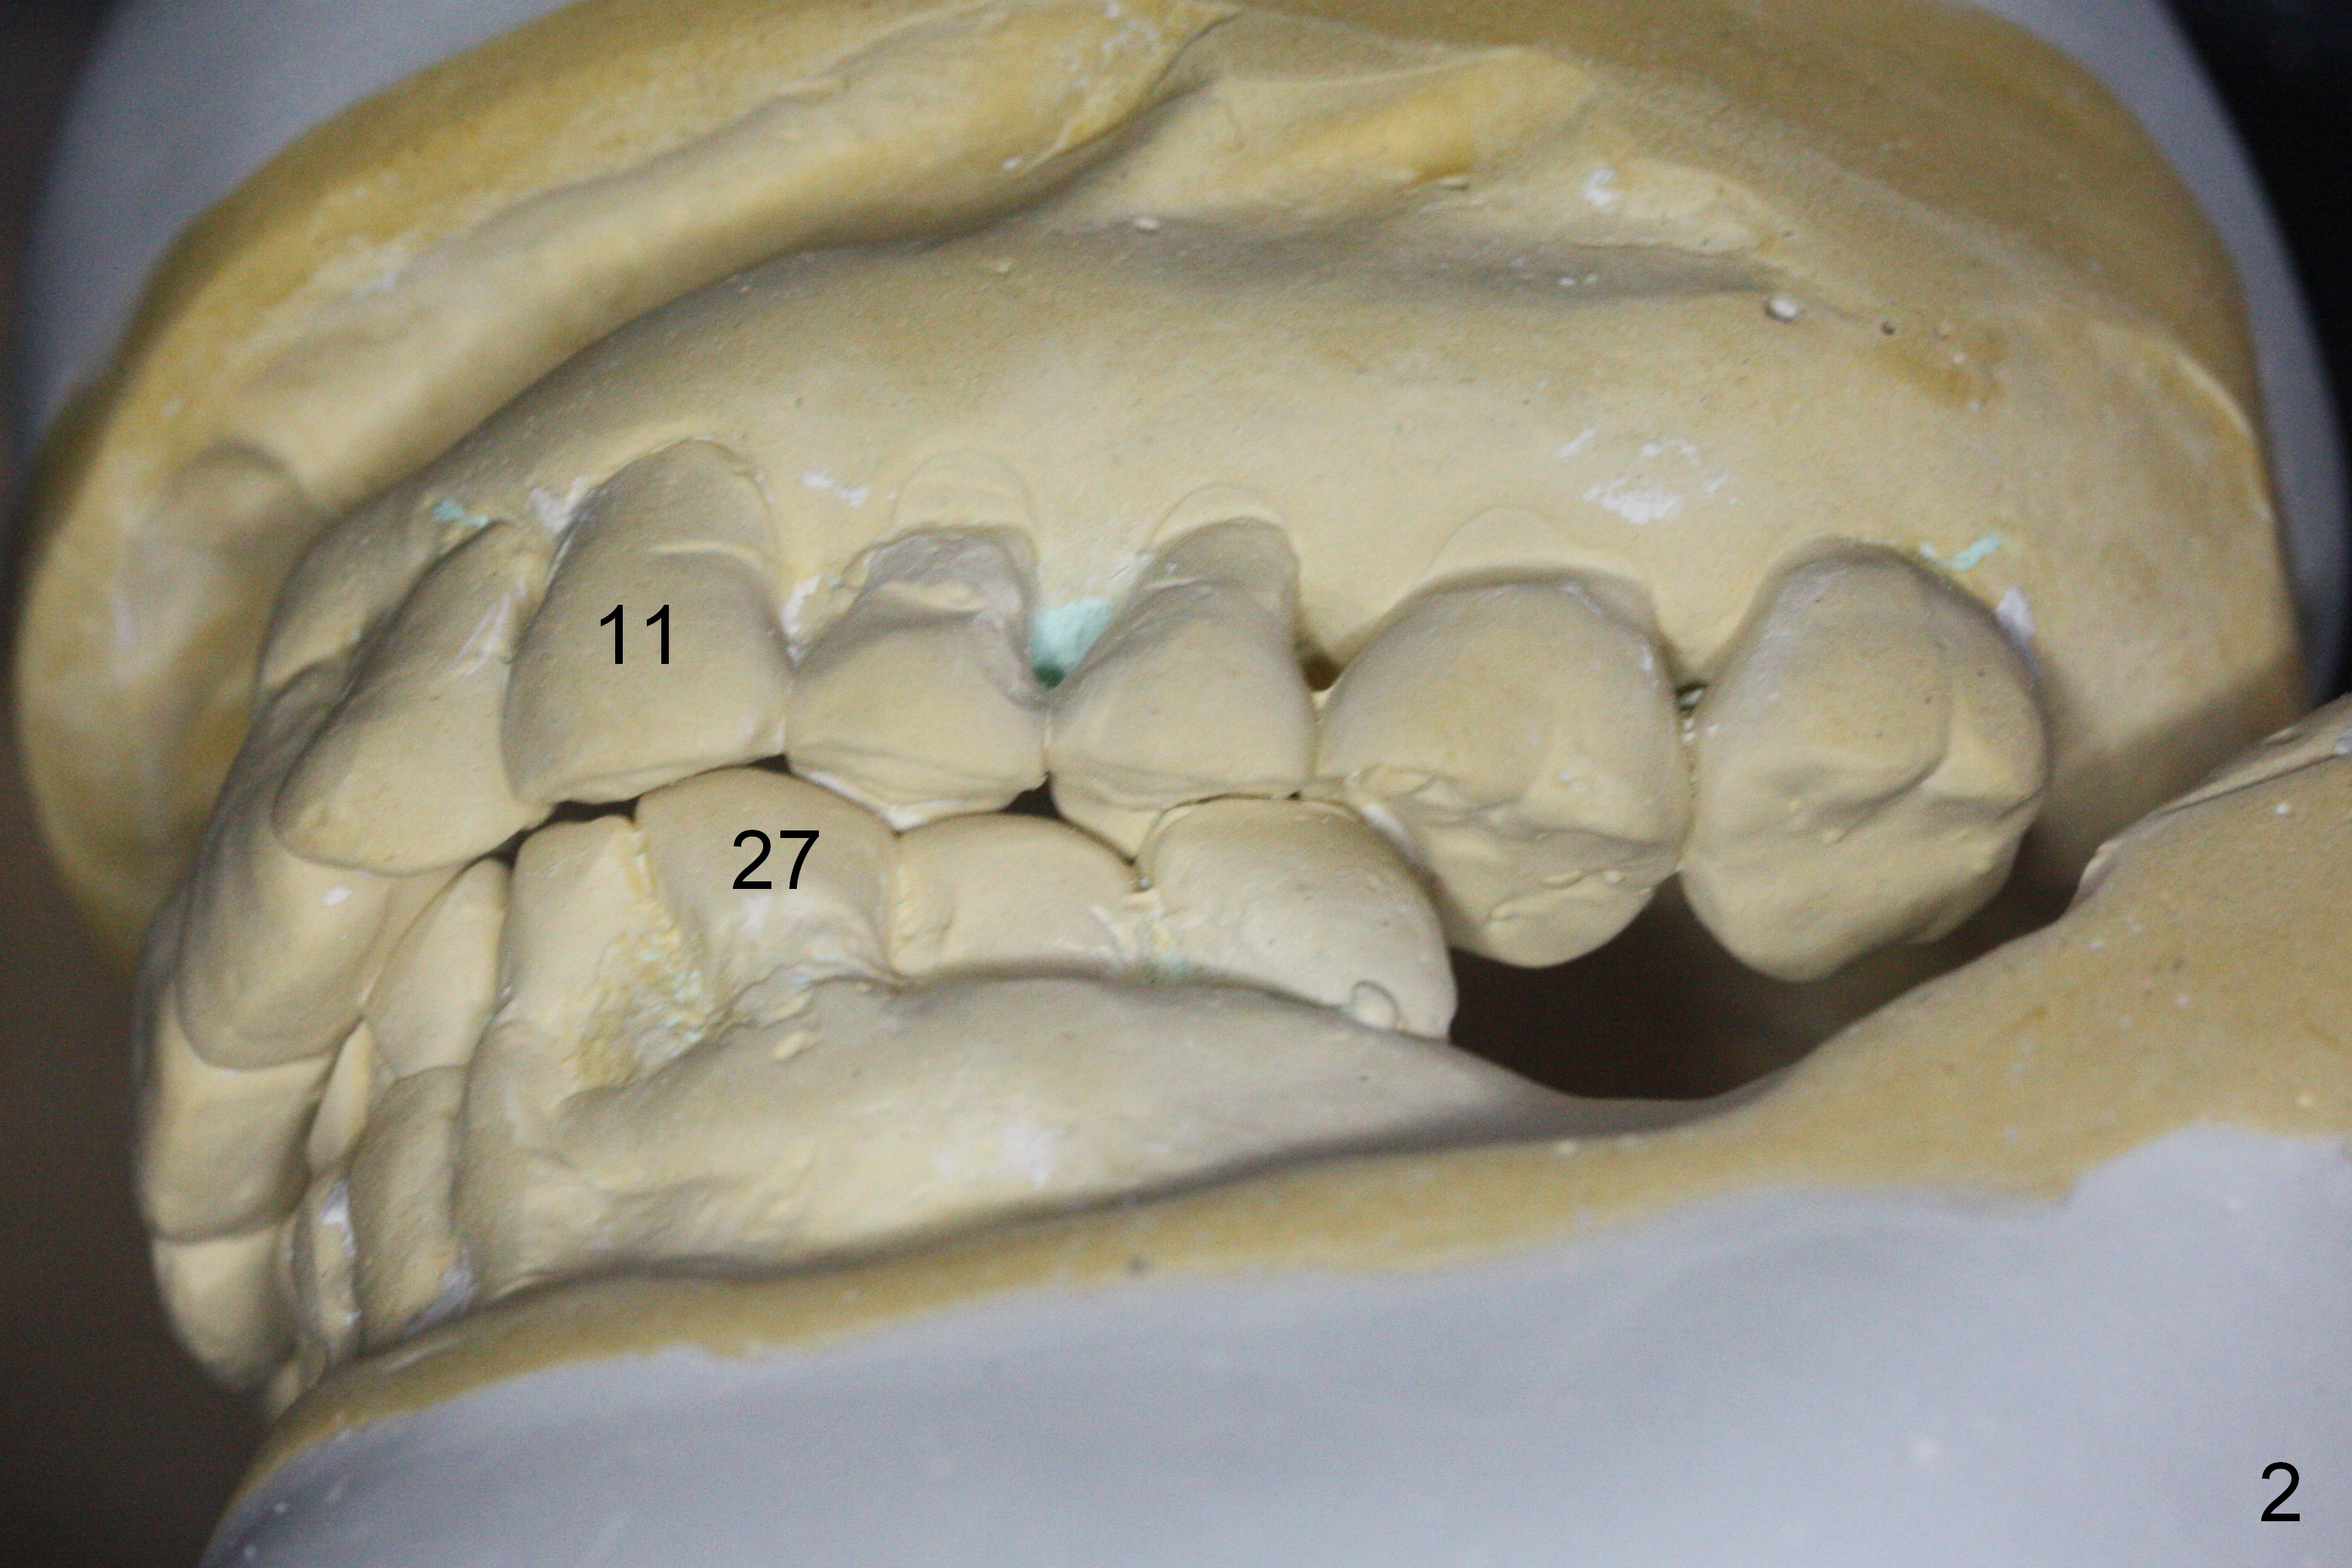

A 73-year-old woman requests implant restoration at #18 and 19 (Fig.1). The left posterior occlusion is Class II (Fig.1,2). The right one is Class I because of small dimension of the restoration at #30 (Fig.3 (premolar)). The normal size of the lower left molars will keep Class II occlusion (Fig.4), which may create cheek bite posteriorly. To correct the occlusion to Class I, move osteotomies to the mesial aspect of waxed-up molars (Fig.6 white circles). Finally a premolar crown and the 1st molar will be placed at #19 and 18, respectively. The supraerupted opposing molars (Fig.5 arrowheads) will to be adjusted when the abutments are placed at the lower molars.